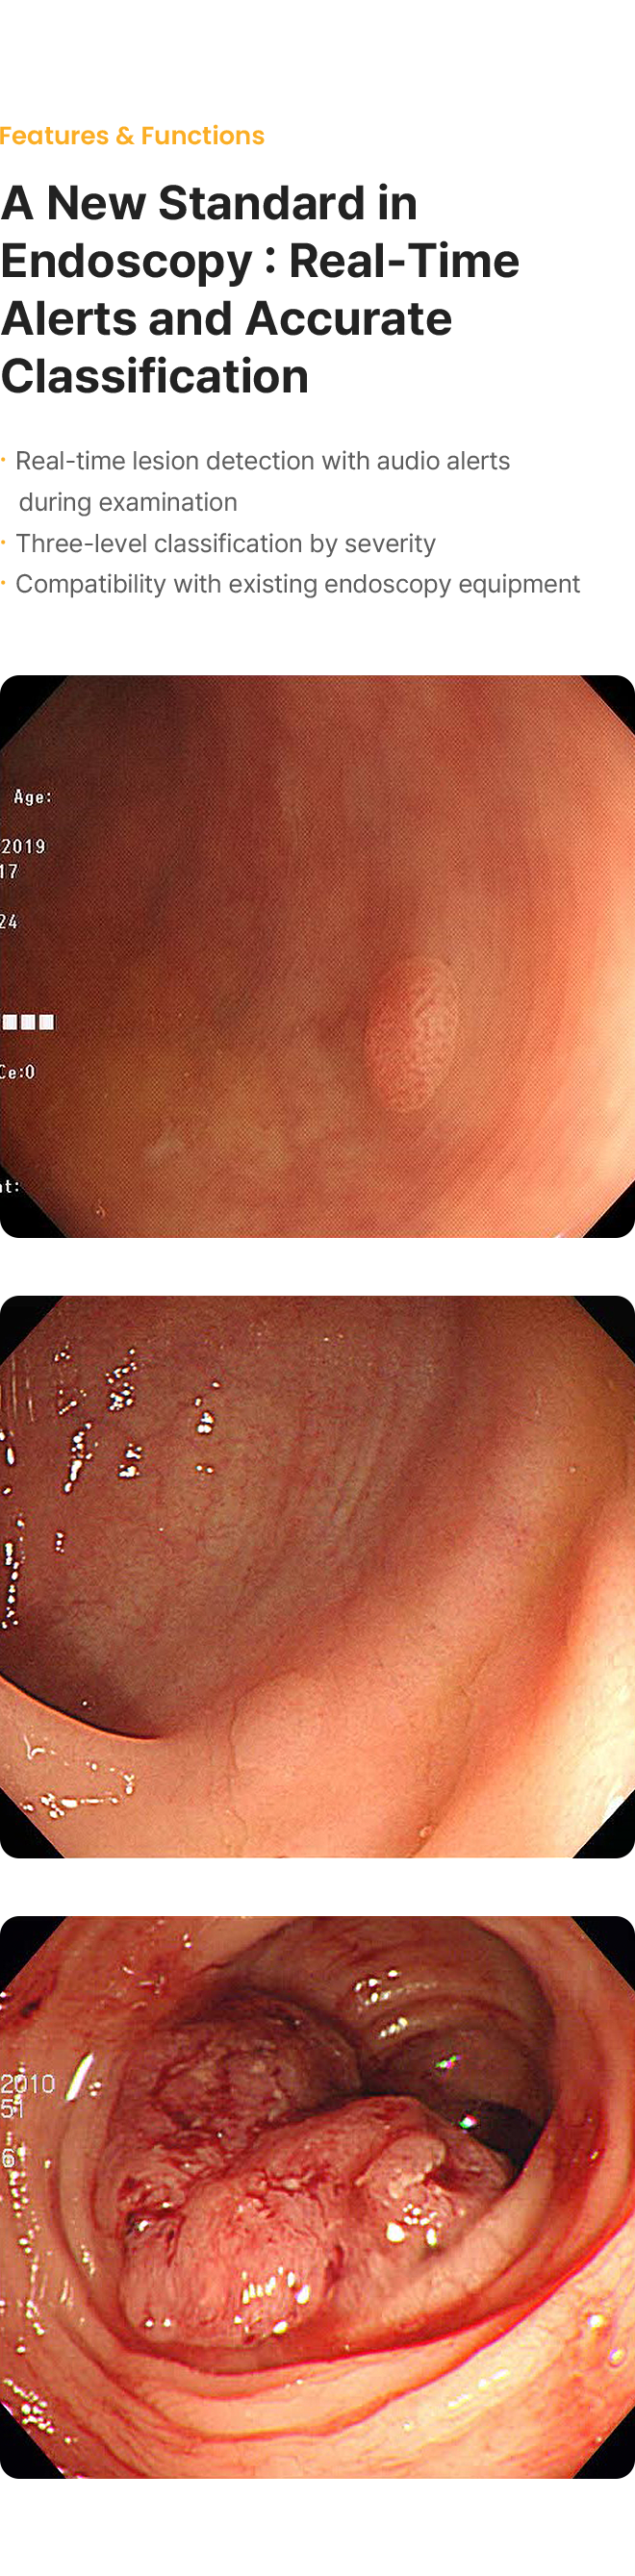

COLON dot AI